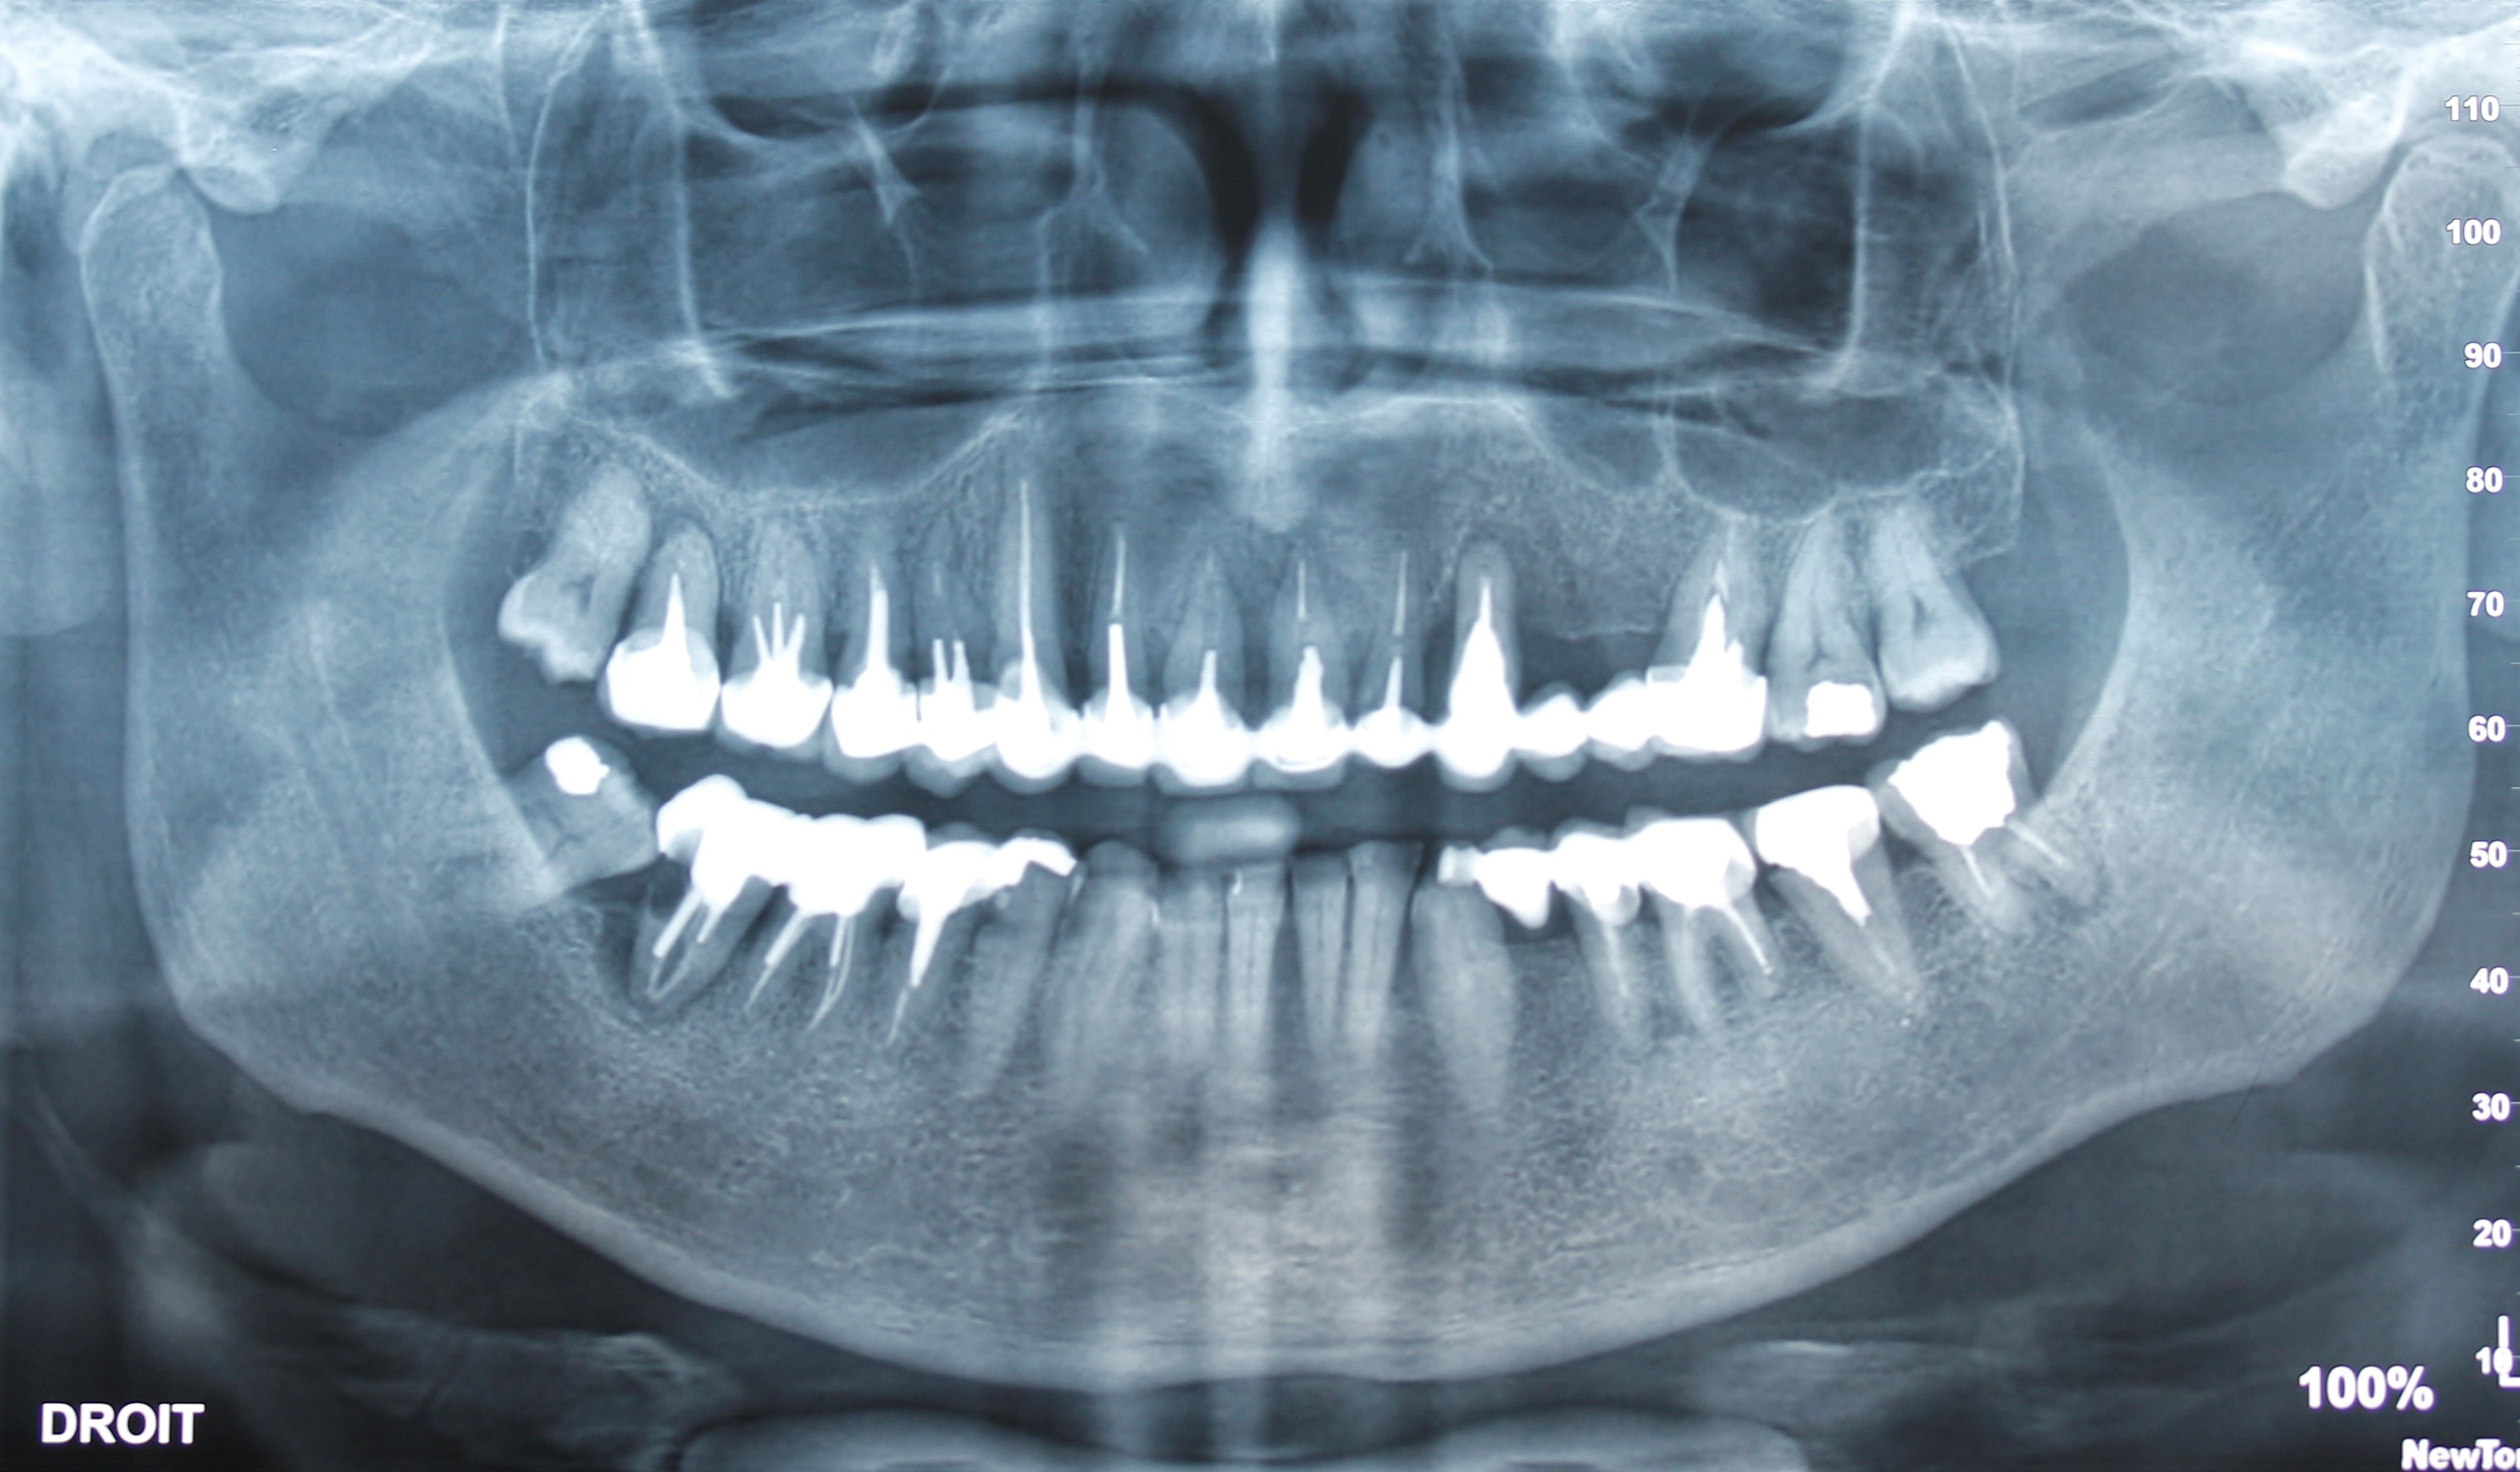

22 cassée, 48 impliquée Proverbe varois?

bien vu , eh oui une fois de plus ça se confirme , t as vu la tronche de 47/48 ? ça pardonne pas .

ça me rappel un sujet ortho récent sur le bien fondé ou non d'extraire des 7 .......... Résultat de la mise en place des dernières molaires sur l'arcade 30 ans plus tard (ici c'est des 8, mais c'est le m^me schéma).....la vrai vie d'omni !

18 dents de dévitalisées!! Le gars, il a vu des dentistes... qu'est-ce qui c'est passé? on lui a jamais parlé de la brosse à dents... ou alors...